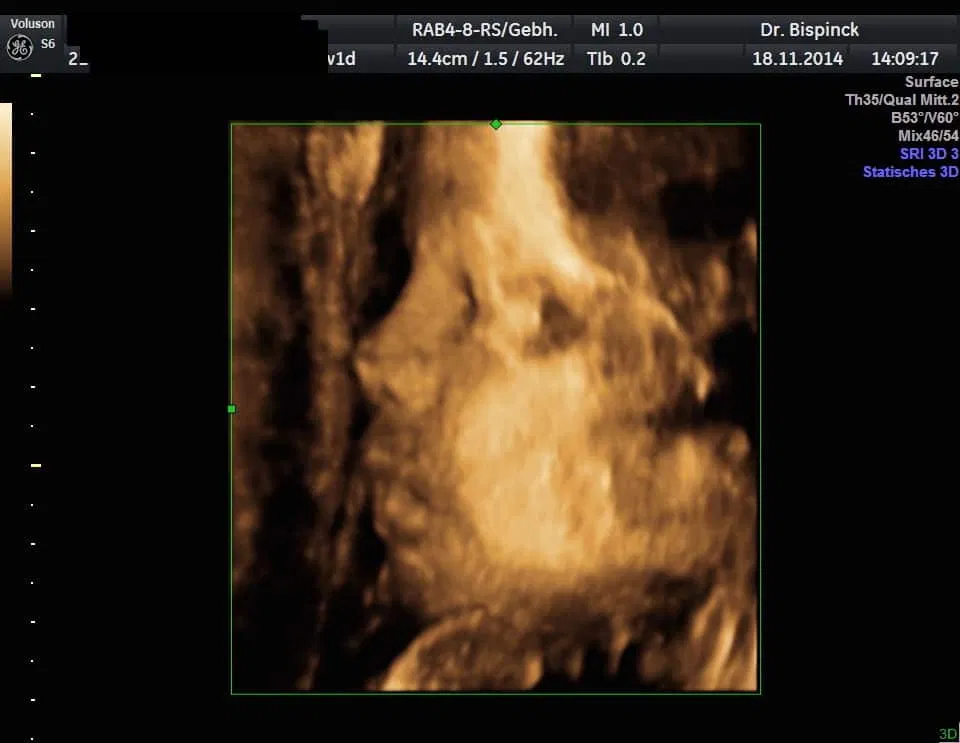

3D/4D Ultraschall

Gerne geben wir Ihnen Bildausdrucke mit.